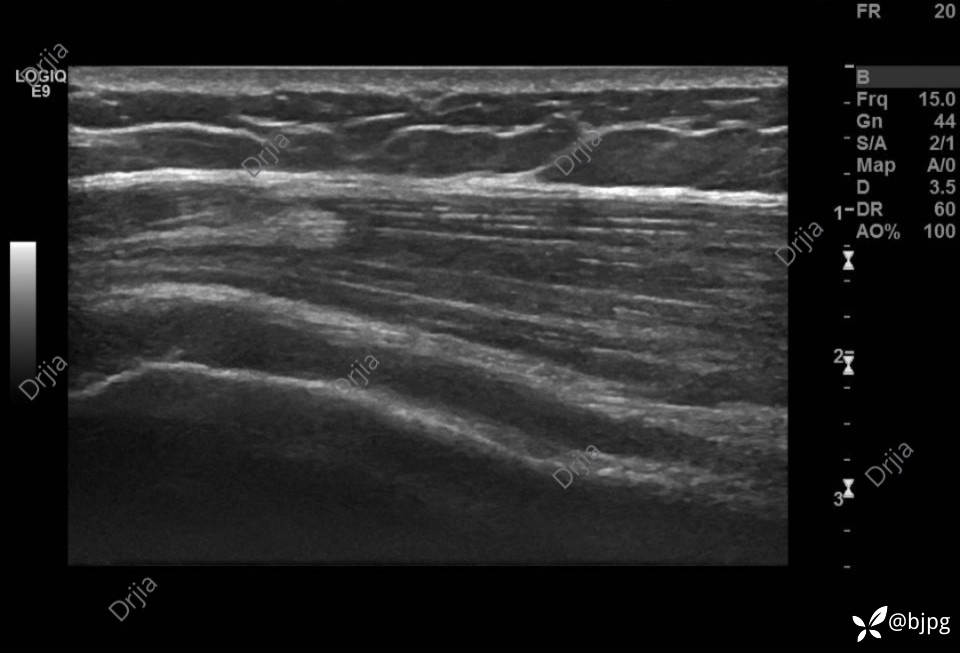

肱二头肌肌腹圆钝,腱腹移行消失